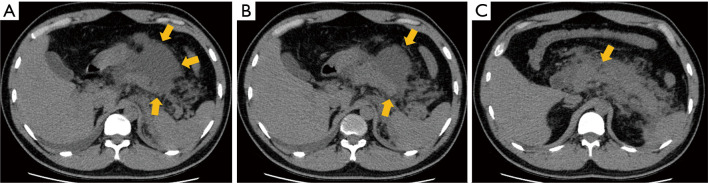

Case description: This case report presents two patients with AP, where a mismatch was observed between clinical and imaging severity assessments. In the first case, laboratory tests suggested mild AP, while computed tomography (CT) imaging indicated severe pathology. In contrast, the second case showed severe AP according to the Acute Physiology and Chronic Health Evaluation II (APACHE II) score, but the CT imaging only revealed mild findings. This clinical-CT mismatch highlights the need for a comprehensive approach to evaluating AP severity, rather than relying on a single assessment method.